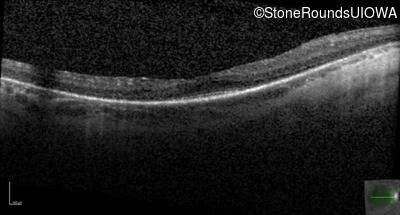

Optical Coherence Tomography - Left - 20/50 -2

Exemplar / OCT Stack

OCT Stack